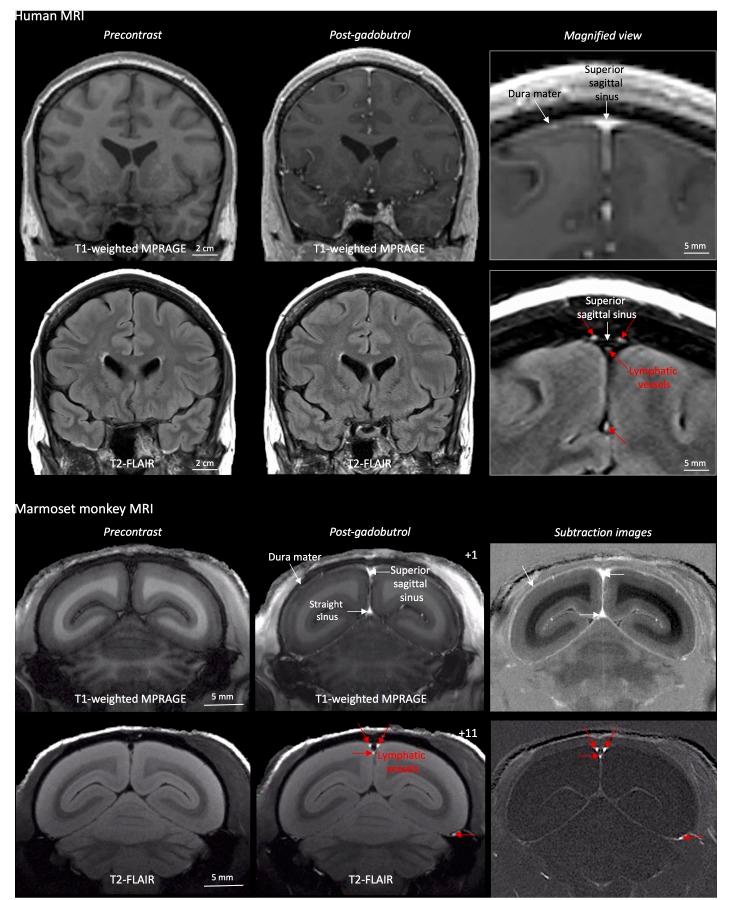

Here, we report the existence of meningeal lymphatic vessels in human and nonhuman primates (common marmoset monkeys) and the feasibility of noninvasively imaging and mapping them in vivo with high-resolution, clinical MRI. On T2-FLAIR and T1-weighted black-blood imaging, lymphatic vessels enhance with gadobutrol, a gadolinium-based contrast agent with high propensity to extravasate across a permeable capillary endothelial barrier, but not with gadofosveset, a blood-pool contrast agent. The topography of these vessels, running alongside dural venous sinuses, recapitulates the meningeal lymphatic system of rodents. In primates, meningeal lymphatics display a typical panel of lymphatic endothelial markers by immunohistochemistry. This discovery holds promise for better understanding the normal physiology of lymphatic drainage from the central nervous system and potential aberrations in neurological diseases.

在这里,我们报告了脑膜淋巴管在人类和非人类灵长类动物(普通狨猴)中的存在,以及使用高分辨率临床 MRI 对其进行非侵入性成像和体内绘图的可行性。在 T2-FLAIR 和 T1 加权黑血成像中,淋巴管增强与钆布醇增强,这是一种具有高倾向穿过可渗透的毛细血管内皮屏障外渗的基于钆的造影剂,但与血池造影剂钆氟塞特不同。这些与硬脑膜静脉窦并行运行的血管的拓扑结构再现了啮齿动物的脑膜淋巴系统。在灵长类动物中,脑膜淋巴管通过免疫组织化学显示出典型的一组淋巴管内皮标志物。这一发现有望更好地理解从中枢神经系统进行淋巴引流的正常生理学以及神经疾病中的潜在异常。